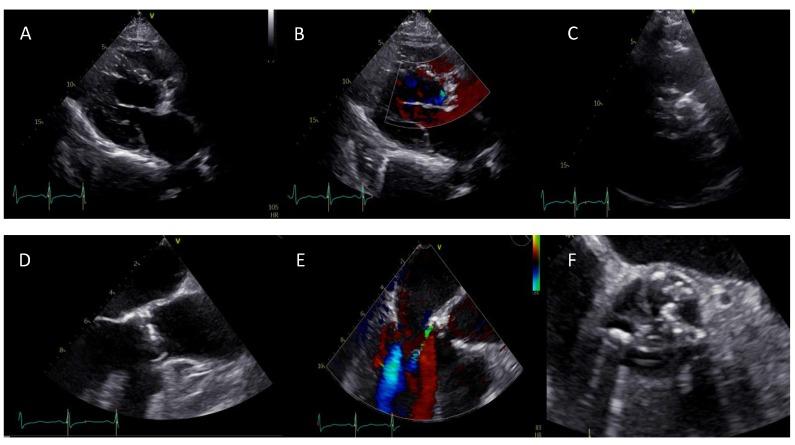

Bicuspid aortic valve (BAV) is the most frequent congenital cardiac abnormality leading to premature aortic valve apparatus dysfunction and is often associated with aortopathy. Therefore, current guidelines recommend a surgical aortic valve replacement (SAVR), even if many patients are deemed inoperable owing to their comorbidities and require alternatives such as transcatheter aortic valve replacement (TAVR). However, BAV variations remain challenging for procedural success. Therefore, the latest development in different imaging modalities (echocardiography, multislice-computertomographie, cardiovascular magnetic resonance) allows in-depth analysis for preprocedural risk stratification, follow up, and patient selection. Furthermore, we shed light on the latest developments in pre- and periprocedural fusion imaging as well as on current and future treatment options.

二叶式主动脉瓣(BAV)是导致主动脉瓣装置过早功能障碍的最常见先天性心脏异常,且常与主动脉病变相关。因此,当前指南推荐进行外科主动脉瓣置换术(SAVR),即便许多患者因其合并症被认为无法进行手术,而需要诸如经导管主动脉瓣置换术(TAVR)等替代方案。然而,BAV的变异对手术成功仍具有挑战性。因此,不同成像模式(超声心动图、多层计算机断层扫描、心血管磁共振)的最新进展使得能够对术前风险分层、随访及患者选择进行深入分析。此外,我们还阐述了术前和围手术期融合成像的最新进展以及当前和未来的治疗选择。